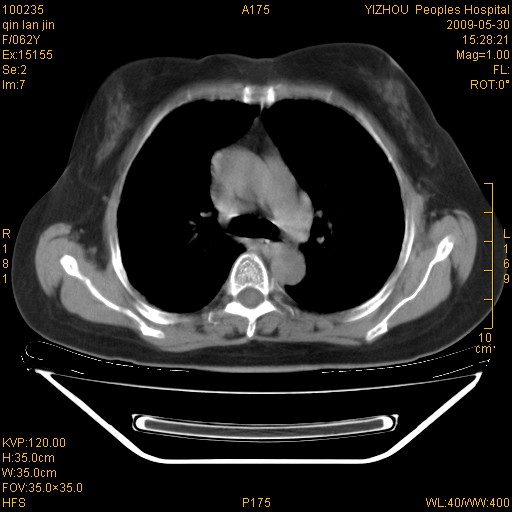

标题: CT20268:肺泡癌?间质性肺炎? [打印本页]

标题: CT20268:肺泡癌?间质性肺炎?

女,62岁,近二年经常咳嗽,近二个月,消瘦、乏力。

两肺弥漫性间质性病变(间质性肺炎伴肺间质纤维化?)。

间质性肺炎伴肺间质纤维化。

纵隔淋巴结大,须排外癌性淋巴管炎